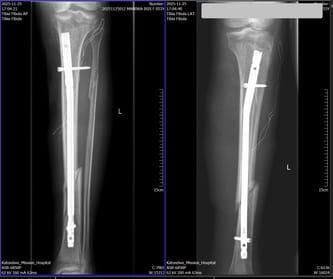

Dzięki Państwa pomocy i niezwykłej hojności mogliśmy zakupić specjalistyczne gwoździe ortopedyczne, które są absolutnie kluczowe w leczeniu ciężkich złamań. I właśnie dzięki nim – dzięki Państwu – w ciągu jednego tygodnia zoperowaliśmy sześciu pacjentów, którzy od wielu tygodni czekali na swoją szansę.